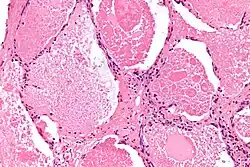

![]() Micrografía de una proteinosis alveolar pulmonar con tinción hematoxilina-eosina. | ||

En la radiografía se muestran patrones radiográficos no específicos de consolidación bilateral y dispersa del parénquima pulmonar. No se muestran signos específicos que sugieran el PAP.[5] Por su parte, en la tomografía se observa un patrón característico conocido como «pavientación» con distribución «en parches o geométrica». El diagnóstico requiere una biopsia pulmonar por cirugía o endoscopia. Ante un examen microscópico, estas muestran presentan «espacios alveolares llenos con un material eosinofílico granular» y positivo a la técnica de Schiff. Igualmente, los exámenes de muestras alveolares obtenidas por lavado broncoalveolar exhiben «tinción granular eosinofílica difusa» con pocos macrófagos y positivo a la técnica PAS.[1] La prueba ELISA para anticuerpos contra el GM-CSF puede emplearse para el diagnóstico de PAP autoinmune.[6]